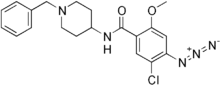

| Formula | C20H22ClN5O2 |

Azapride is the azide derivative of the dopamine antagonist clebopride synthesized in order to label dopamine receptors.[1][2] It is an irreversible dopamine antagonist.[2]